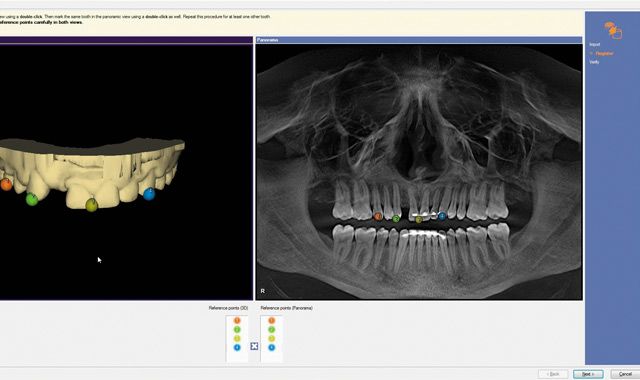

Fig. 06 The *.ssi file from the digital wax-up was integrated within the GALILEOS implant software.

Fig. 07 The virtual wax-up was then integrated into the CBCT scan.